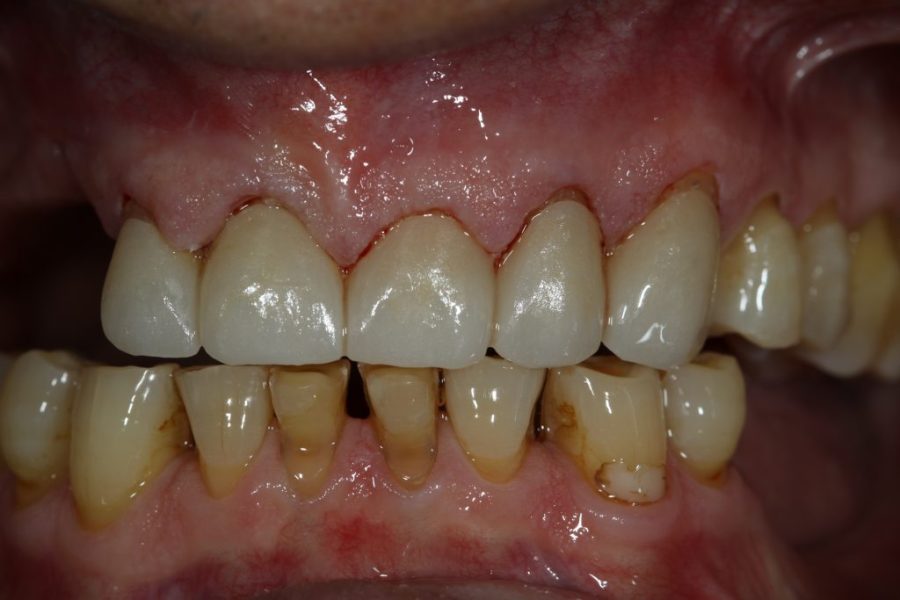

George’s Story: Customised Zirconium Bridges

George, hesitant at first, came to fix his front teeth at his wife’s insistence. After two appointments, he received zirconium bridges, giving him a full and natural smile—while preserving his signature gap.